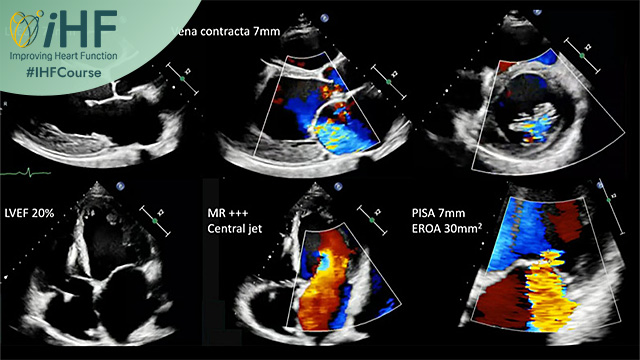

Refractory heart failure: combining oral therapy and device is key